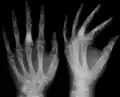

The disease consists of the growth multiple enchondromas which usually develop in early childhood. The growth of these enchondromas usually stops after skeletal maturation.[4] The affected extremity is shortened (asymmetric dwarfism) and sometimes bowed due to epiphyseal fusion anomalies. Bone lesions generally present as cellular during childhood and become more solitary over time. People with Ollier disease are prone to breaking bones (fractures) and normally have swollen, aching limbs. However, many cases of solitary enchondromata go unnoticed due to lack of symptoms. Enchondromas are commonly found in the phalanges, metacarpal, and metatarsal bones in patients of Ollier disease due to the affinity of enchondromas to long tubular bones such as the femur and humerus. A unilateral distribution of bone lesions is usually observed but bilateral distributions or a singular extremity can occur as well. Approximately a third of the cases show some form of physical deformities of bowing or abnormal limb lengthening.

Abnormal bone growth such as shortening or thickening and deformity may be observed in patients of Ollier disease. These bone lesions are visible at birth using radiography but are usually not screened or examined for until clinical manifestations present during early childhood. However, some patients may exhibit no signs of any symptoms.[1] One study found thirteen to be the mean age of diagnosis in patients with Ollier disease. In an X-ray, there would normally be the presence of several homogeneous lesions of an oval or elongated shape with bone edges that are slightly thickened.[3] With age, these lesions may calcify and appear as diffusely minute spots or stippled. Fan-like septations or streaks would be indicative of the presence of several enchondromas. Early detection and consistent and repeated monitoring is important in order to prevent and treat any potential bone neoplasms.